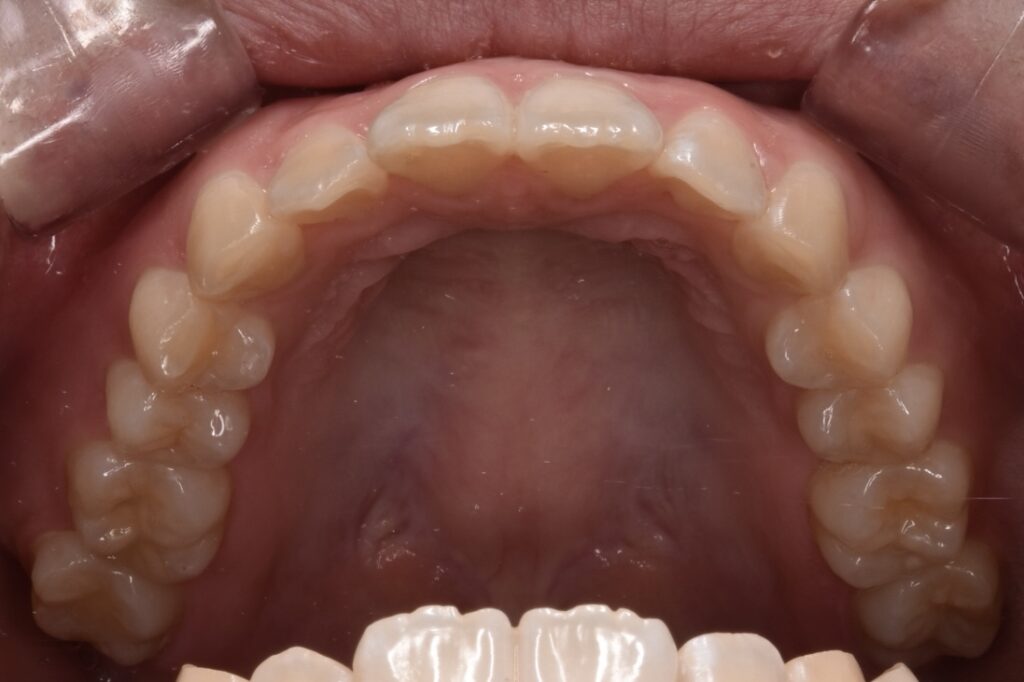

治療後